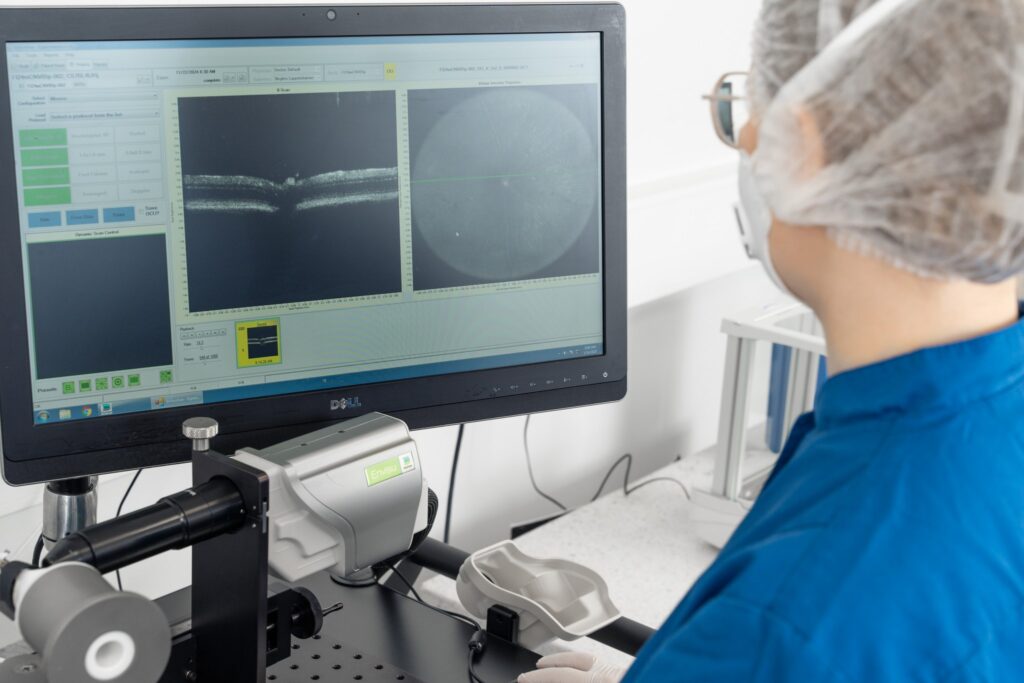

– Retinal thickness assessment with SD-OCT imaging

Customised in vivo functional assessment of different aspects of vision